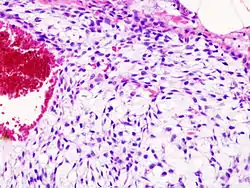

Histopathology

Imaging studies - including radiographs ("x-rays"), computerized tomography (CT), and magnetic resonance imaging (MRI) - are often used to make a presumptive diagnosis of chondrosarcoma.[11] However, a definitive diagnosis depends on the identification of malignant cancer cells producing cartilage in a biopsy specimen that has been examined by a pathologist. In a few cases, usually of highly anaplastic tumors, immunohistochemistry (IHC) is required.

There are no blood tests currently available to enable an oncologist to render a diagnosis of chondrosarcoma. The most characteristic imaging findings are usually obtained with CT.